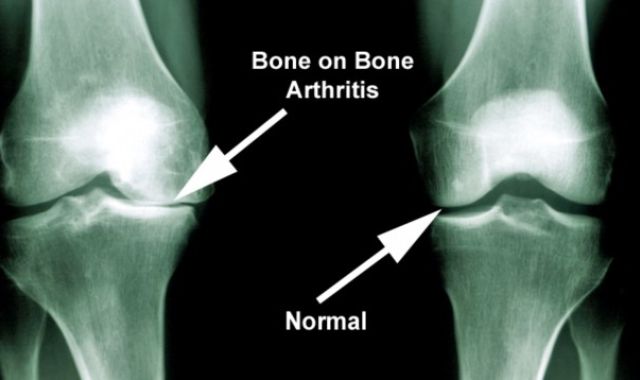

What is Osteoarthritis?

Attached video explains simply what osteoarthritis is and how it manifests as a painful... -